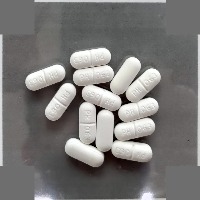

Pill Segmentation v1 Computer Vision Project

Pill Segmentation

downloadsClasses (181)

A description for this project has not been published yet.